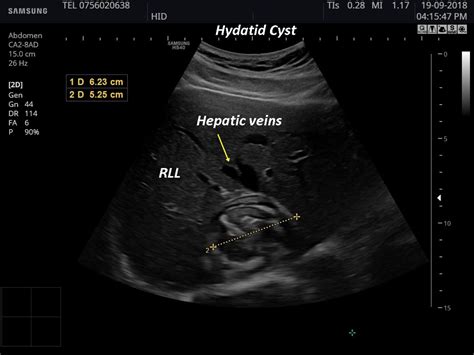

A hepatic cyst ultrasound is a crucial diagnostic tool for evaluating liver cysts. This imaging technique uses high-frequency sound waves to create detailed images of the liver and its structures. The ultrasound can help determine the size, shape, and location of the cysts, as well as assess their impact on surrounding tissues.

The images obtained from a hepatic cyst ultrasound are reviewed by a radiologist, who looks for specific characteristics of the cysts. Key factors that are assessed include:

• The size and number of cysts.

• The presence of any solid components within the cysts.

• The impact of the cysts on surrounding liver tissue.